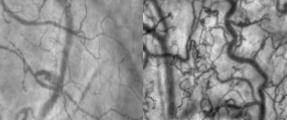

Researchers have investigated direct clinical evaluation by using dark field imaging of capillary beds under the tongue of septic and healthy subjects for signatures of microcirculatory dysfunction associated with sepsis. Our published results, in collaboration with Beth Israel Deaconess Medical Center, have shown that machine learning and vision can learn higher-order hierarchical diagnostic and prognostic features for rapid and non-invasive diagnosis of sepsis using these dark field microcirculatory images. A neural network capable of distinguishing between images from non-septic and septic patients with more than 90% accuracy is reported for the first time. This approach can help physicians to rapidly stratify patients, facilitate rational use of antibiotics, and reduce disease burden in hospital emergency rooms.

In previous studies, microcirculation dysfunction was experimentally induced in animal models with drugs and other agents followed by Sidestream Dark Field (SDF) imaging. SDF imaging is a non-invasive imaging modality and has been used to track changes in the microcirculation on mucosal surfaces. SDF uses green polarized light with wavelength of 550 nm which is absorbed by hemoglobin and makes red blood cells visible. The distinguishing parameters and measurements associated to microcirculation include MFI (Microcirculation Flow Index), PVD (Perfused Vessel Density), TVD (Total Vessel Density) and PPV (Portion of Perfused Vessels). These measurements require identification of vessels in microcirculation video frames. Several software systems have been developed to analyze the microcirculation images and videos for these measurements, but often fail to provide desired results. Marking of hand engineered features on each frame of the video is required at some stage of analyses and is time consuming and not accurate.

To our knowledge, this is the first study that successfully classifies human microcirculation image data using a deep neural network. In this work, we implement a CNN to analyze microcirculatory dysfunction captured by dark field imaging in human patients and distinguish between septic and nonseptic images with high accuracies.